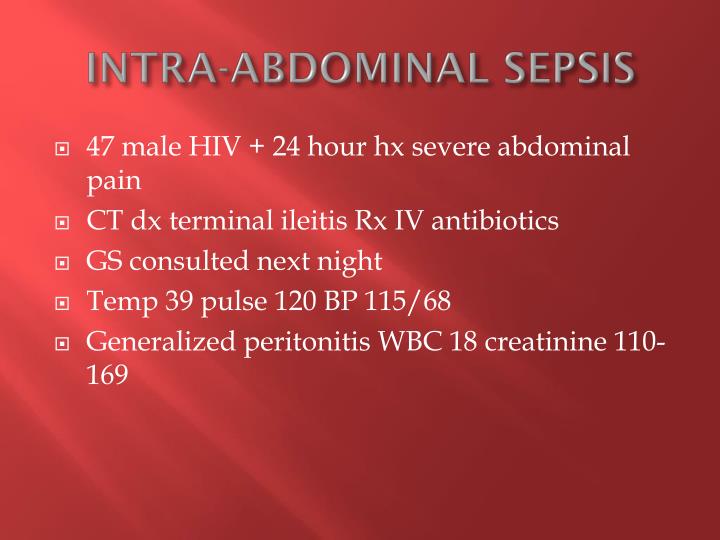

A missed case of intraabdominal sepsis BMJ Case Reports

Source: casereports.bmj.com